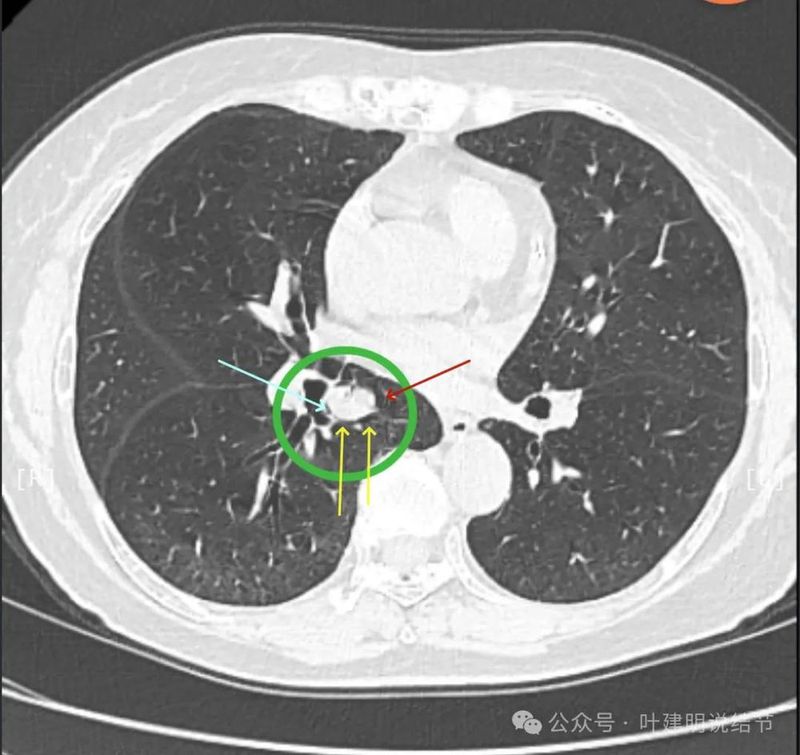

先看患者提供的2024年2月份的CT影像:

病灶出现,在右下叶支气管旁边,轮廓清楚,此层似磨玻璃密度。

表面似分叶状,密度不纯,邻近血管略有弯曲向病灶。

实性密度,边缘光滑,与背段支气管亚段贴着。

天蓝色箭头示病灶与支气管之间有缝隙,但贴的较近;黄色箭头示支气管管腔;红色箭头示病灶,边缘光滑。

支气管受压,但无明显破坏;与支气管之间紧贴位有的位置仍有缝隙;病灶边缘光滑。